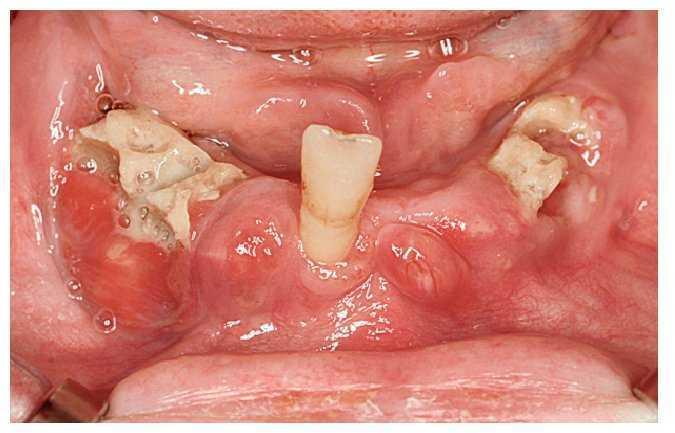

Las necrosis maxilares y mandibulares se caracterizan por la aparición de zonas óseas expuestas como resultado de intervenciones odontológicas o debido a microlesiones. Es frecuente que después de extracciones dentarias se genere una herida tórpida que no cicatriza, con zonas óseas expuestas, no cubiertas ni por mucosa ni por un coágulo sanguíneo. Estas zonas óseas presentan una coloración amarillenta-grisácea y la mucosa adyacente está eritematosa (fig. 3). A diferencia de una alteración de la cicatrización normal, este cuadro puede acompañarse inicialmente de poco dolor, pero en una fase más avanzada el paciente puede sufrir un dolor intenso en esta zona. Además, llama la atención una halitosis marcada, lo que afecta aún más al paciente.

Figura 3. Hueso expuesto y tumefacción de la mucosa adyacente a la osteonecrosis.

A esto se pueden añadir diferentes grados de movilidad dentaria, trastornos de la sensibilidad sobre todo en el área del mentón y del labio inferior, y también fístulas. En casos de afectación extensa pueden aparecer trayectos fistulosos extraorales (figs. 4a a 4c).

Figura 4a. Osteonecrosis muy marcada con áreas extensas de hueso expuesto, fístulas múltiples y tumefacciones mucosas.